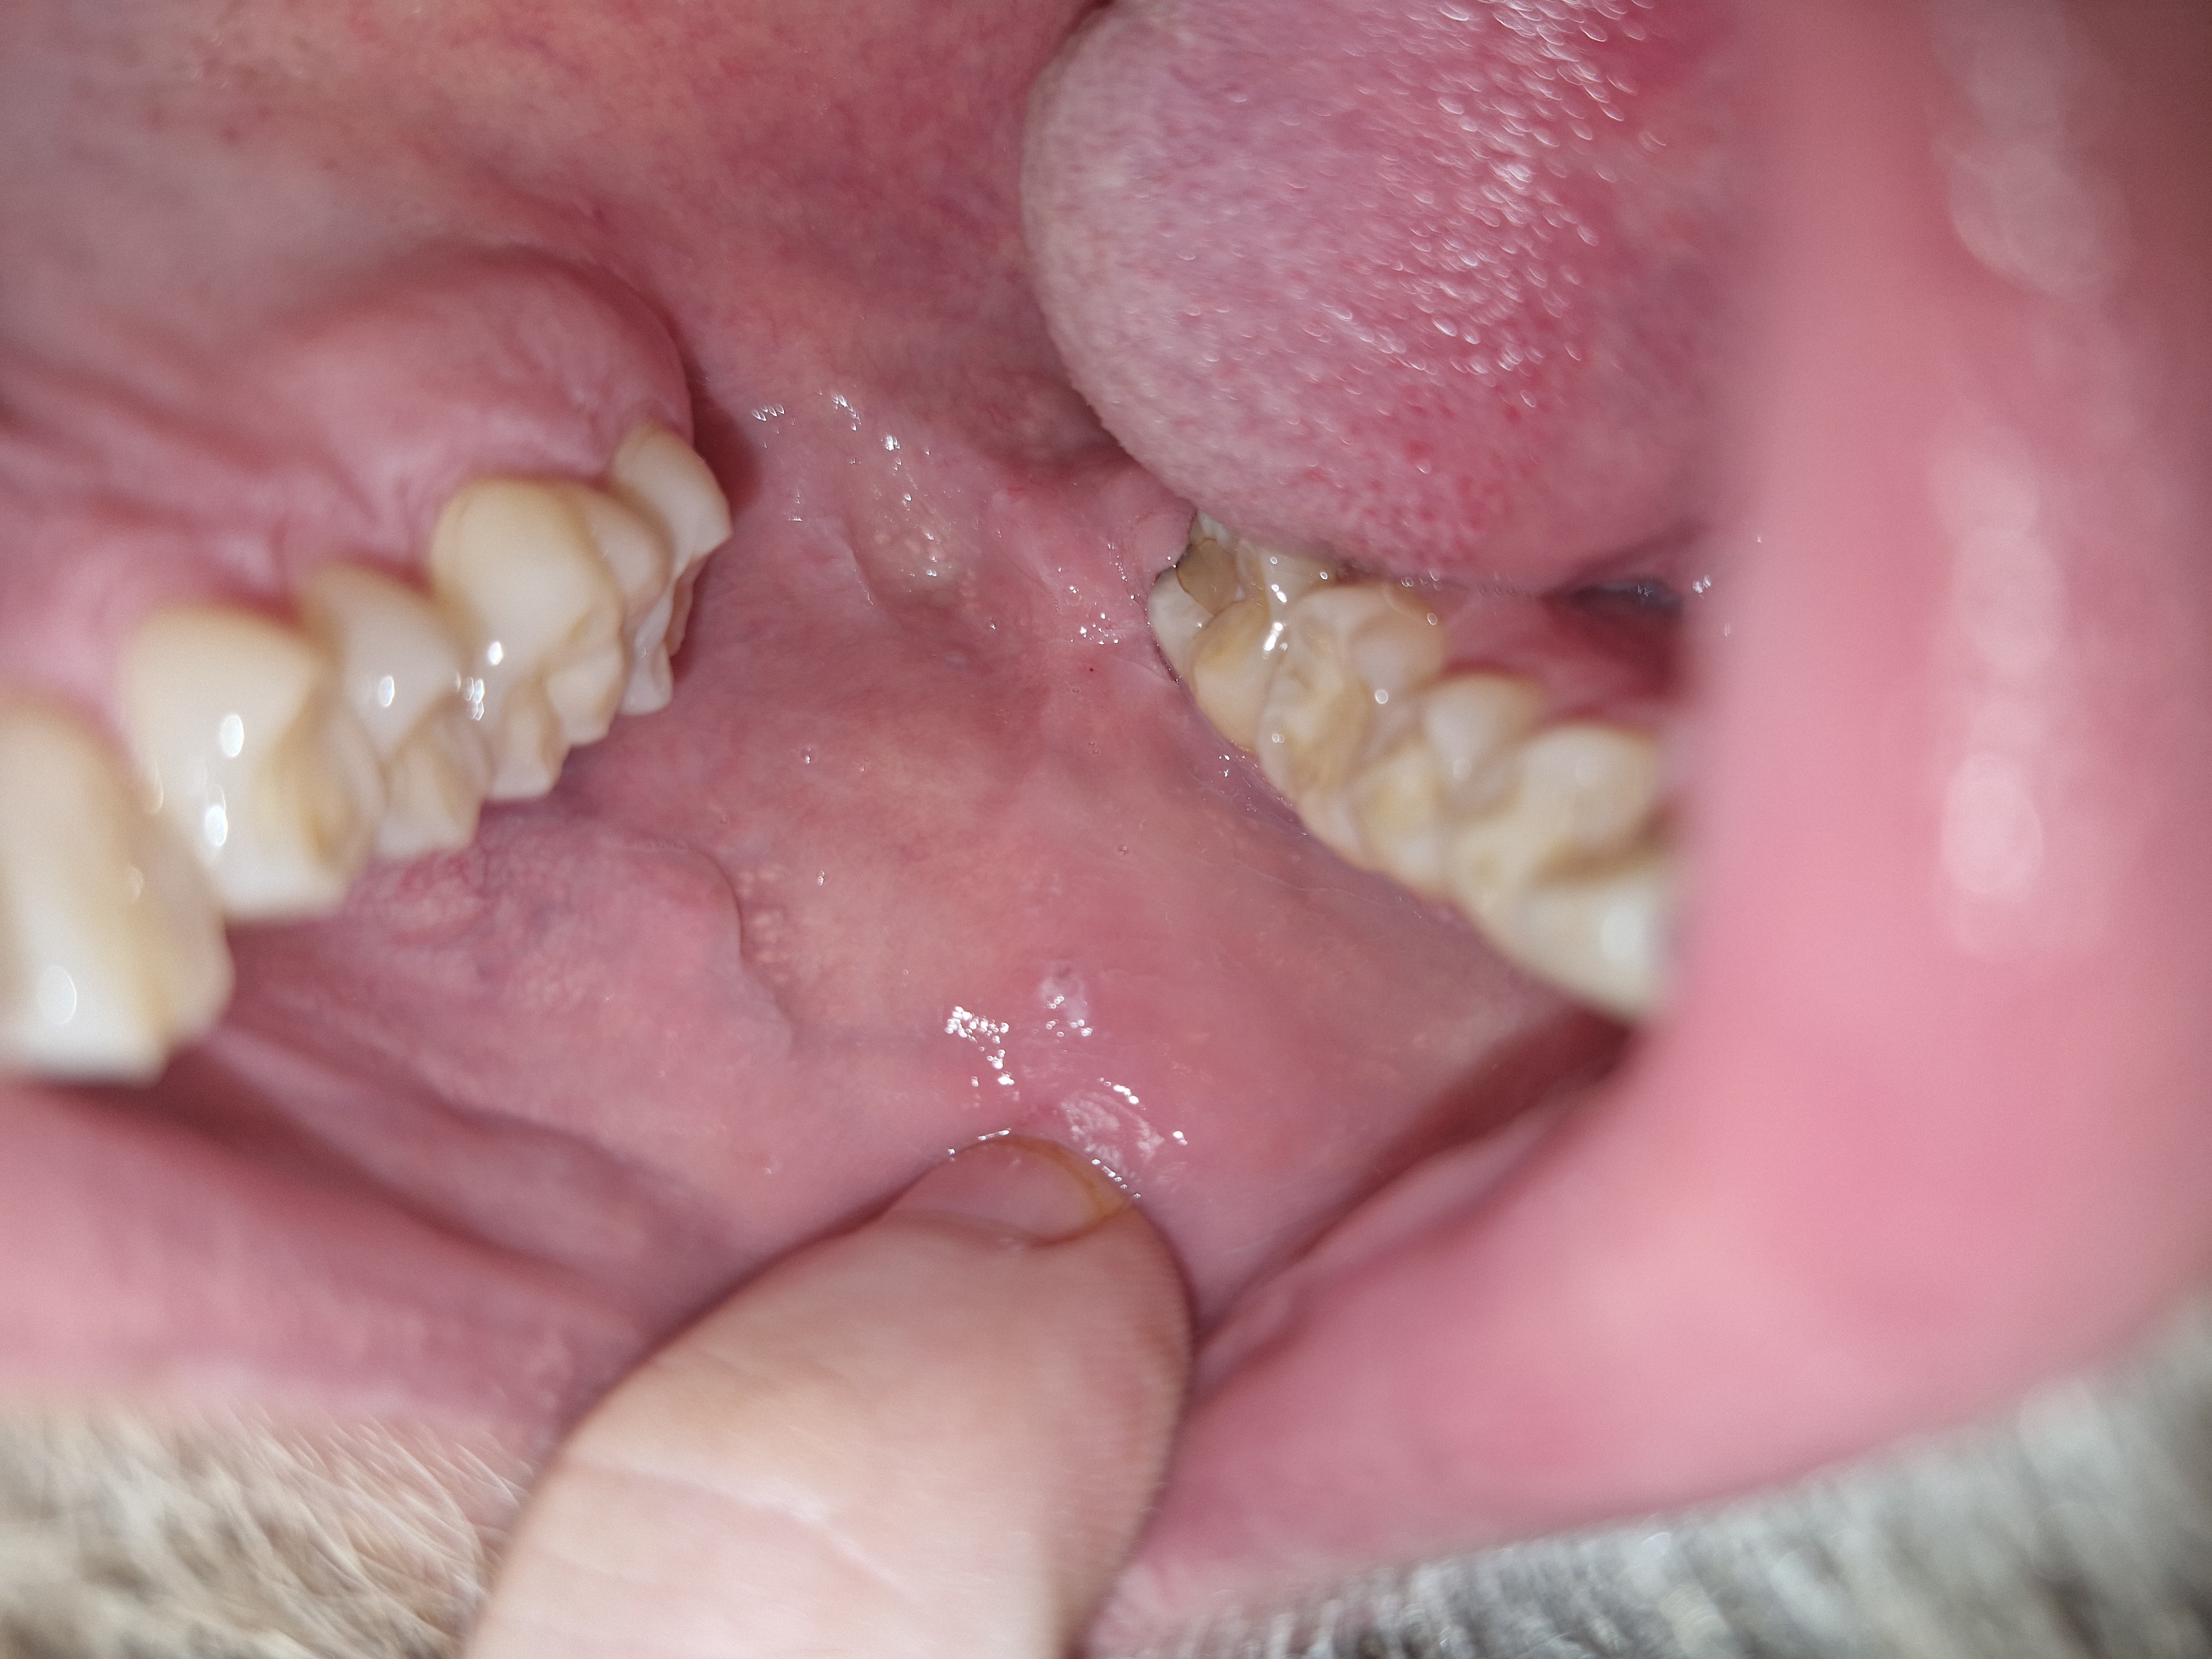

Hoi ik heb een vraag ik ben een man van 27 jaar en kwam sinds vandaag er achter dat ik een klein wit vlekje heb aan de binnenkant van mijn rechter wang. Ik bijt regelmatig op mijn wang dus dacht misschien dat het dat is maar heb nog nooit eerder zo wit vlekje daardoor gehad. Op internet lees ik veel over leukoplakie en andere dingen en begon mezelf zorgen te maken vandaar dat ik de vraag hier laat omdat het ook vrijdag avond is en ik nu niet tot maandag een afspraak kan maken bij de tandarts

Het plekje doet verder geen pijn en is naar mijn idee ook niet hard wat zal dit kunnen zijn aften of toch iets anders ?